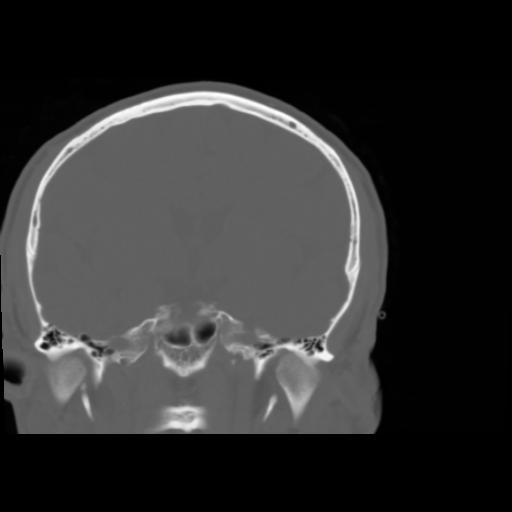

5 CEREBRO,,Coronal,3.000,CEREBRO,Coronal,